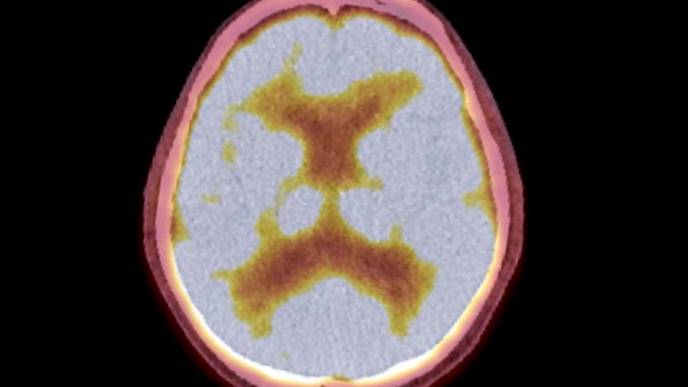

Brain metastases are the most prevalent adult central nervous system tumors, with 20% to 30% of cases resulting from breast cancer patients, particularly those with triple negative and HER2 amplified disease. Managing breast cancer metastases in the brain is challenging, with only 20% of patients with breast cancer brain metastases surviving beyond five years.